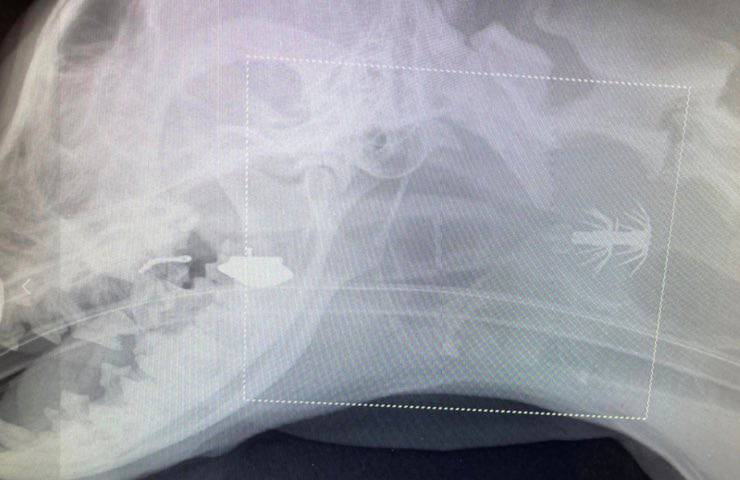

Nala avrebbe iniziato a grattarsi ininterrottamente la zona ferita cercando di rimuovere con alcuni colpi di tosse forzati l’appuntito intruso, ma invano poiché l’arpione a forma di pesce le era rimasto incastrato nella gola. Nala è stata trasportata nella clinica veterinaria più vicina dove è stata sottoposta ai raggi X. Dai risultati della radiografia il personale medico ha capito come intervenire. L’arpione era bloccato nella faringe, così i veterinari hanno operato per un’anestesia e una veloce incisione. Dopo l’operazione Nala ha ripreso conoscenza dimostrando con il suo dolce sguardo tutta la sua gratitudine.

Le immagini – in diretta dalla Tasmania – del temibile arpione sarebbero inoltre in grado di dimostrare che si tratta di un oggetto oltremodo mascherabile e che, da una prima ricerca, risulta essere stato realizzato per praticare la pesca indisturbata di alcune determinate specie di calamari.